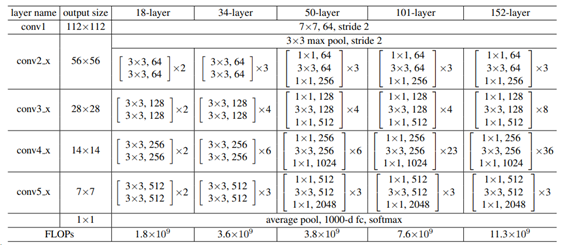

AI 모델 상세 설명서 다운로드 AI 모델 다운로드ResNet 50 기반 구현

주요 분류 모델은 (He et. al., Deep Residual Learning for Image Recognition, CVPR 2016) 결과에 기반하여 적용

주요 학습을 위한 구현 상세는 다음과 같음